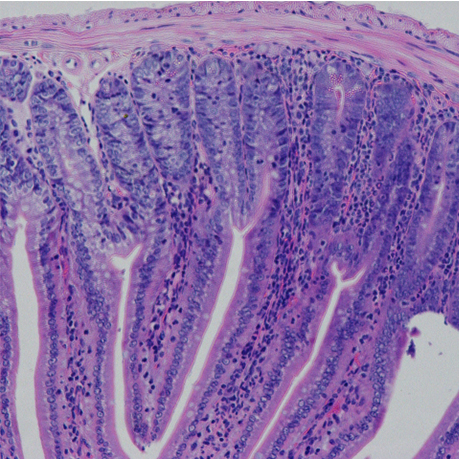

小鼠胃部与小肠病理切片HE染色

小鼠小肠病理切片与染色(1)

小鼠小肠病理切片与染色(2)